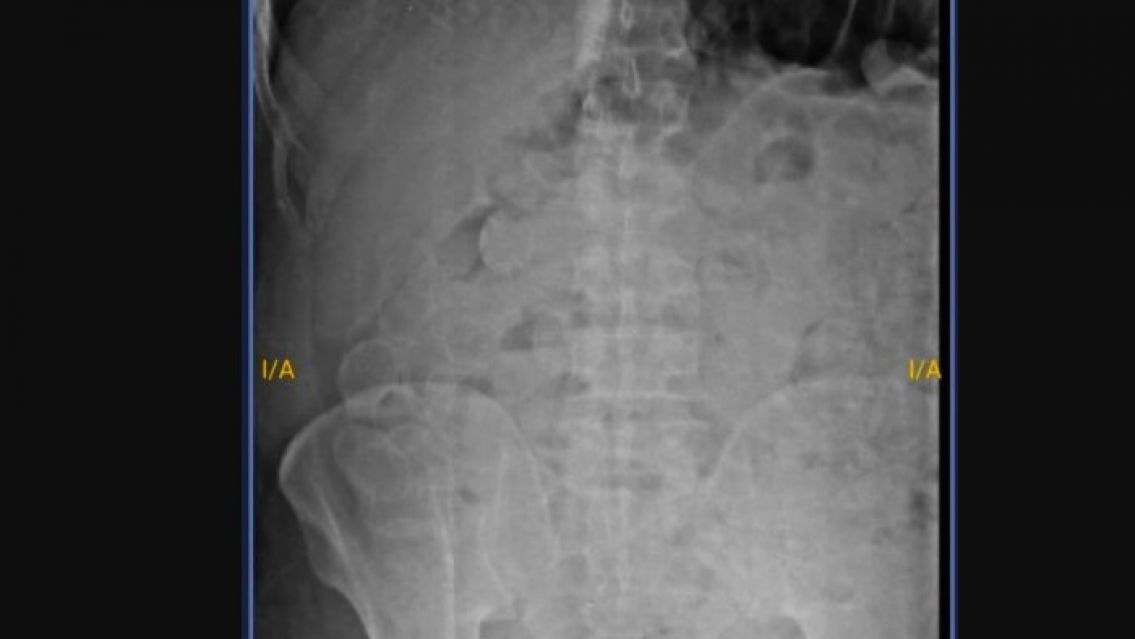

Un interno del Complejo Penitenciario Federal de Jujuy fue internado de urgencia en el hospital "Pablo Soria" de San Salvador de Jujuy tras presentar un cuadro agudo de dolor abdominal. El hombre, de 30 años y oriundo de Salta, confesó haber ingerido más de 180 cápsulas que contendrían marihuana durante una salida transitoria.

En el nosocomio, fue diagnosticado preliminarmente por consumo de sustancias y quedó internado en observación bajo estricta custodia. Según indicaron fuentes oficiales, el objetivo es monitorear la expulsión del material ingerido para su posterior análisis.